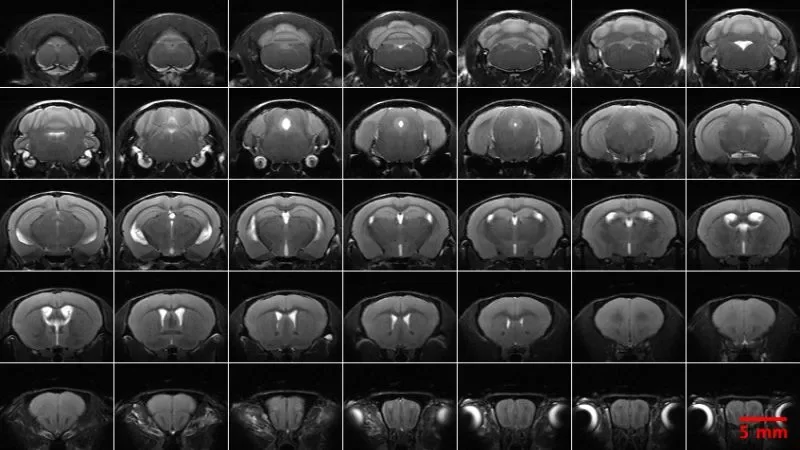

| NBP Pre-pulse Inhibition/Startle Reflex | PCI MRI-Anatomical |

| NBP Rotarod | PCI MRI-Angiography |

| NBP Social Approach (3-Chamber) | PCI MRI-Diffusion Tensor Imaging |

| NBP Spontaneous Alternation-Visual Cues (Y-Maze) | PCI MRI-Diffusion Weighted Imaging, Isotropic |

| NBP Tail Withdrawal | PCI MRI-Neurite Orientation Dispersion and Density Imaging |

| NBP Von Frey | PCI MRI-Neuroanatomical |

| PCP Auditory Brainstem Response | PCI MRI-Neuroanatomical, Isotropic |

| PCP Blood Pressure, Non-Invasive | PCI MRI-Resting State Functional (rsfMRI) |